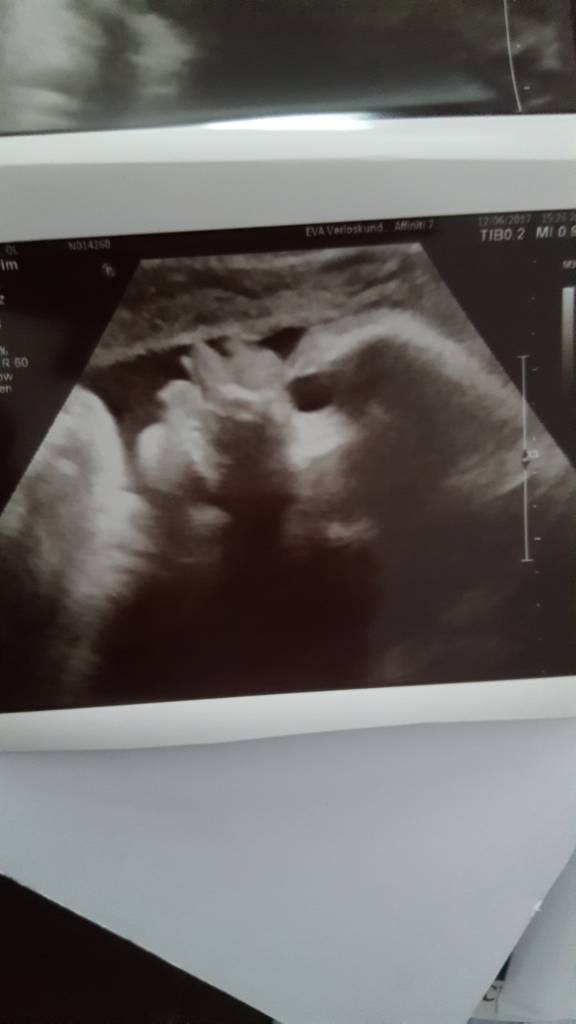

Dostalam foto z usg..Pani sie mogla lepiej postarac..ale wazne ze foto jest..

Napiszcie mi co sadzicie..czy te moje dziecie ma takie ogromne wargi czy tylko tak zdjecie wyszlo..?